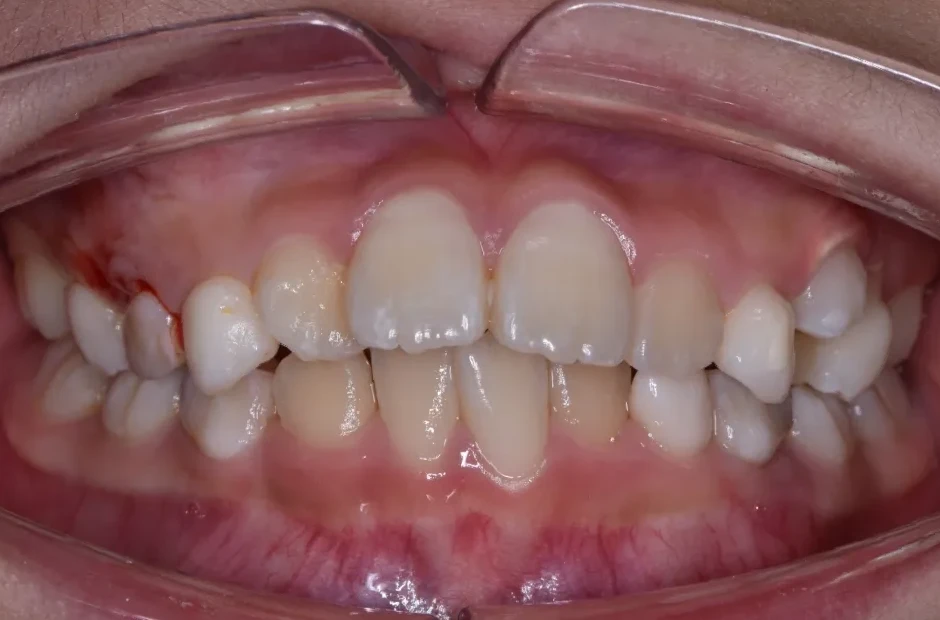

反対咬合

| 診断名・主訴 | 前歯反対咬合 |

|---|---|

| 年齢・性別 | 12歳・男性 |

| 治療期間・回数 | 1年半 18回 |

| 治療に用いた主な装置 | リンガルアーチ(前方誘導弾線) |

| 抜歯部位 | なし |

| 治療費 | 35万円(税抜) |

| リスク・副作用 | 装置による違和感・疼痛・歯肉退縮・歯根吸収・虫歯のリスクなど |

治療前

治療後